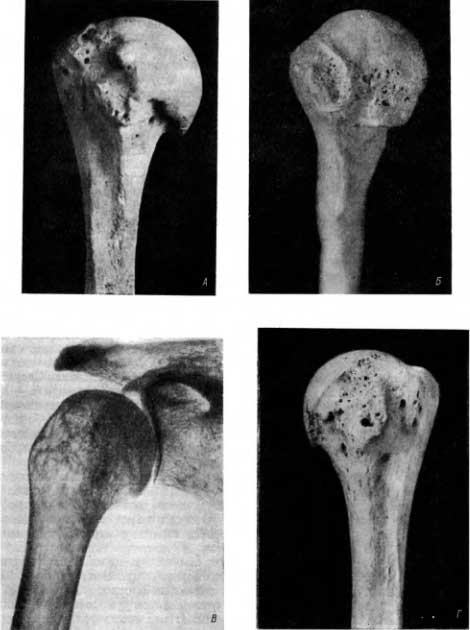

В плечевом суставе нередко наблюдается деформирующий артроз с поражением головки плечевой кости и суставной впадины на лопатке. Краевые костные разрастания, особенно на головке, могут быть очень велики (рис. 7, А).

Приведем несколько примеров. На головке правой плечевой кости зрелой женщины из погребения в Саркеле имеются краевые костные разрастания-проявления деформирующего артроза в главном плечевом суставе (рис. 7, А). Верхняя поверхность большого бугорка отличается желтоватым блеском, она как бы отполирована. Поверхность малого бугорка неровная, с шиповидным выступом; суставная поверхность акромиона склерозирована (рис. 7, А, Б, В). Это проявления деформирующего артроза как в главном плечевом суставе, так и в добавочном субакромиальном суставе. На головке левой плечевой кости и на большом и малом бугорках этой кости также видны проявления деформирующего артроза.

Рис. 7. А — деформирующий артроз в главном плечевом и в добавочном субакромиальном суставах (вид спереди); поммеровские узлы в виде ямок различных размеров; Б — деформирующий артроз субакромиального сустава; дегенеративно-дистрофическое поражение обоих бугорков плечевой кости, поммеровские узлы (вид снаружи); В — дегенеративно-дистрофическое поражение обоих бугорков той же плечевой кости в рентгеновском изображении; поммеровские узлы; Г — дегенеративнодистрофическое поражение малого бугорка.

На левой плечевой кости зрелой женщины из погребения в Саркеле в главном плечевом суставе нет существенных изменений; то же самое на сочленяющейся поверхности большого бугорка. Имеются значительные изменения на резко уплощенном малом бугорке (рис. 7, Г), где видны крупное кистовидное образование (4x3 мм) и 2 мелких (1.5x1.5 мм). Таким образом, кистовидная форма дегенеративно-дистрофического поражения сустава может наблюдаться и в субакромиальном суставе. Как было указано, кистовидная форма дегенеративно-дистрофического поражения сустава протекает в общем тяжелее, чем те его формы, которые характеризуются наличием проявлений деформирующего артроза, т. е. краевыми костными разрастаниями и склерозом суставных поверхностей, представляющих некоторое приспособление к новым условиям. При кистовидных формах, как было сказано, проявления компенсации к новым условиям либо вовсе отсутствуют, либо слабо выражены.